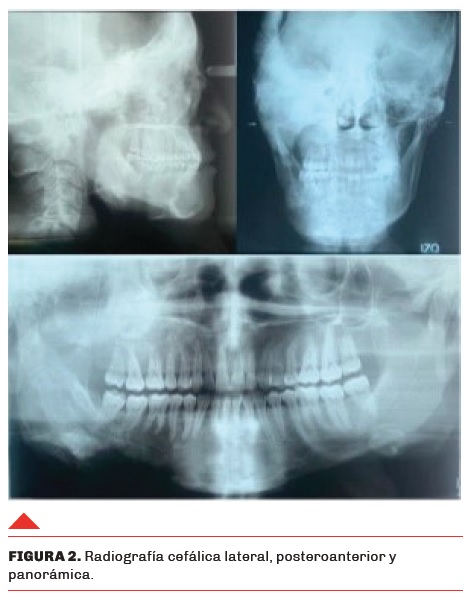

Se procede a solicitar estudios de extensión tales como radiografía cefálica anterior, cefálica lateral, radiografía panorámica y de fotografía para poder llevar a cabo la predeterminación convencional del caso (Figura 2). Con estudios solicitados se realiza trazado comparativo con lado contralateral y, por tanto, logrando identificar exceso de tejido fibroóseo para ser resecado, se lleva a cabo toma de medidas en sentido craneocaudal y anteroposterior a nivel mandibular para poder determinar cantidad de resección mediante osteotomía/ostectomía a realizar mediante molde preformado de acetato (Figura 3).